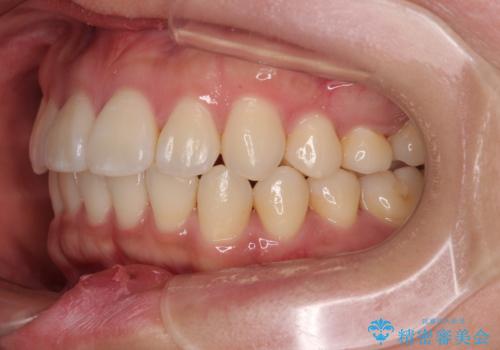

「歯並びと正中が整って、自信をもって笑えるようになった」

と大変ご満足のお言葉をいただきました。

デコボコと正中のずれを改善した矯正治療